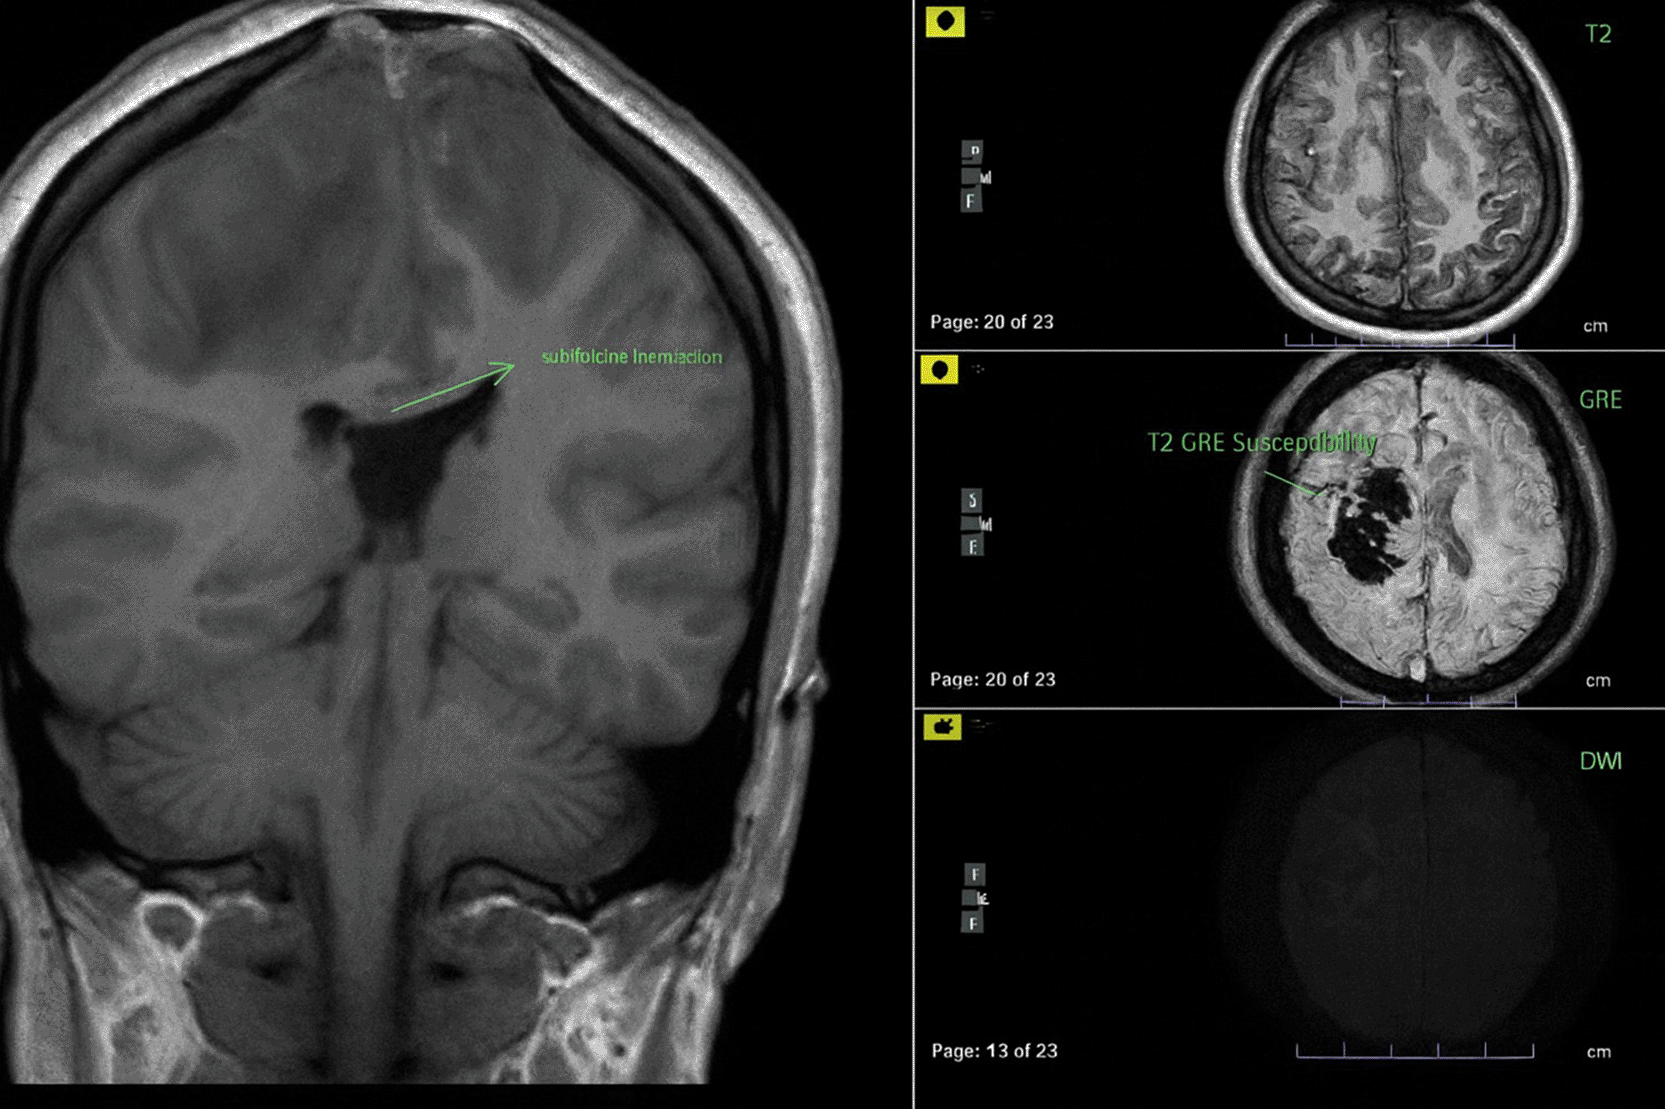

The patient in the ICU remained conscious (E4V5M6) but experienced another seizure. Therapy was administered as a loading dose of mannitol at 1 g/kg body weight, followed by a maintenance dose of 0.5 mg/kg four times daily, continuous magnesium sulfate at 2-3 mg/kg/hour, citicoline at 500 mg three times daily, and sedation with dexmedetomidine at 0.5-0.7 mcg/kg/hour. The patient exhibited clinical and hemodynamic enhancement. On the subsequent day (ICU H-3), the patient reiterated complaints of intense headache and agitation (E3V5M6), which were succeeded by seizures and diminished consciousness. A neurological assessment revealed left hemiparesis, with right/left motor strength recorded at 5-5/4-4, and no nuchal rigidity was observed. A CT scan of the head revealed a “Dens sign” alongside intracranial hemorrhage (ICH) encircled by considerable edema in the superior sagittal sinus region, accompanied by subarachnoid hemorrhage. Nimodipine at a dosage of 6x60 mg and a hypertonic saline loading dose of 3 mg/kg, subsequently followed by 1 mg/kg body weight every 8 hours, were administered. The left side limbs exhibited a decline in strength to 5-5/2-2, accompanied by diminished motor function in the right side limbs (4-4/2-2). The CT scan of the head without contrast (NCCT, Figure 1) prompted a consultation with the neurology division, followed by a D-dimer test yielding a result of 4870 ng/ml. An MRI and MRV of the head revealed a hemorrhagic venous infarct in the right-left parietal lobe (dominant right, volume approximately 15.5 cm), accompanied by perifocal edema that displaced the right-left lateral ventricle inferiorly, resulting in subfalcine herniation to the left side due to thrombosis with anteromedial occlusion of the superior sagittal sinus ( Figures 2-3). Anticoagulant therapy commences with an initial dose of 5000 IU of low molecular weight heparin (LMWH), followed by a maintenance dose of 1.8 IU/kg body weight, and a consultation with the neurosurgery division for decompression craniectomy.

ICH is seen from rupture of the superior sagittal vein.

The lesion produced significant local mass effect with effacement of the surrounding sulcus and left subfalcine herniation (3.8 mm).

MRV = magnetic resonance venogram.